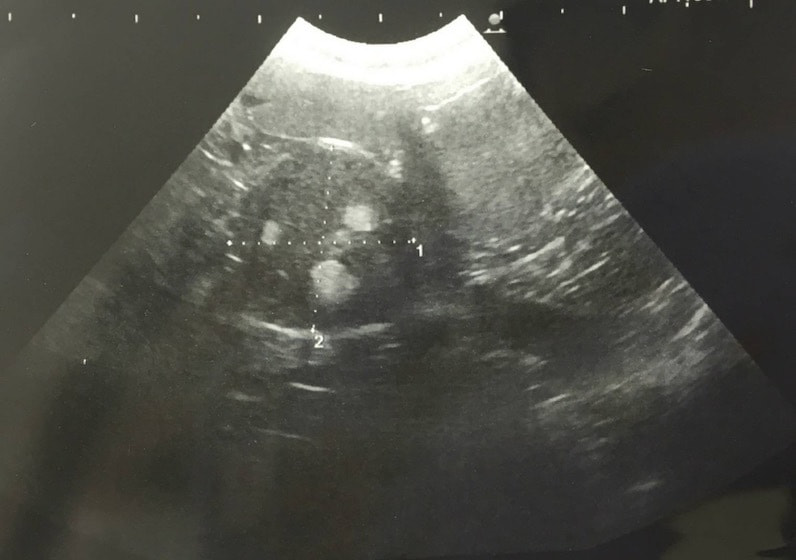

エコー検査